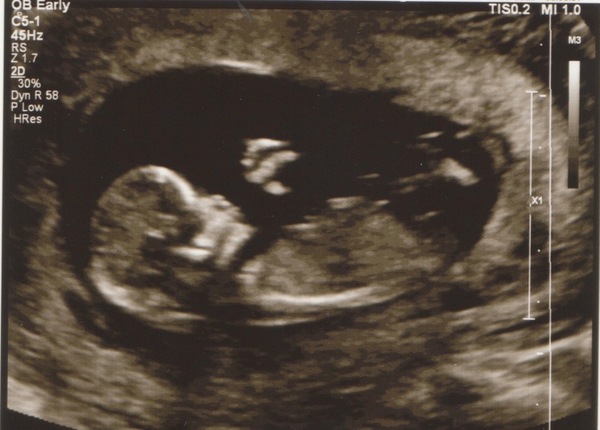

December 2016 babies... 2nd trimester in sight

Loving all the good news and lovely scans today!!! Wishing you all the best for tomorrow Hannah X

Wowee, what an exciting day all 'round! Very happy to see all the lovely scan pics and that you're all doing well. Smile

Yay for the beautiful and healthy scans!

So one happy healthy scan. Now been put forward to 13weeks so EDD is13th December.

Hope everyone is okay and loved seeing the scans.

So so lovely to see all of your pictures!

Lovely scans today girls.

So lovely to see everyone's beautiful scan pictures!

Our scan went well today, due date is the 19th December! Baby was being a bit of a tinker, she had me in all sorts of positions, I even did some start jumps!! Got there in the end! Now the nervous wait for the screening results! Hope every one else's went well! XSmile

Been a tough day at work but commute home made much cheerier by all these lovely scan pics. A real bumper crop today! Congrats all.

First scan for me today too. Due date now 10th Dec, if you please update the list KitKat. I'd managed to keep calm but I'm elated now. I still can't believe that we are so lucky to have a healthy little person living inside me!

Lovely to see so many scans today. Fingers crossed for the rest of you lovely ladies having scans this week

Lovely to see all these 12w scans now! Still not sure I'm going to make it through to 20w, might need to book another private one.....